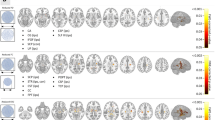

For the insular cortex and the lateral orbitofrontal and superior temporal gyri, the overall ANOVA F-test in all mTLE laterality types was significant after Bonferroni adjustments (p < 0.0019). In t-tests between pairs of laterality types, the coherence laterality showed significant differences in insular cortex for the right versus left mTLE cases, right mTLE versus control cases and left mTLE versus control cases (p < 0.0167; Fig. 4). However, for the lateral orbitofrontal and superior temporal gyri, significant differences were found in coherence laterality only for the right versus left mTLE cases and the right mTLE versus control cases (p < 0.0167). Figure 5 shows the MEG mean coherence in the insular cortex and the lateral orbitofrontal and superior temporal gyri overlaid upon the MNI registered brain (Xia et al. 2013) for the right and left mTLE patient cohorts. Figure 6 shows the MEG coherence laterality in these regions for individual patients.

The MEG mean coherence in insular cortex and the lateral orbitofrontal and superior temporal gyri overlaid upon the MNI registered brain (Xia et al. 2013) in the right and left mTLE patients where significant differences in coherence laterality between the right and left mTLE patients are demonstrated. The spheres and lines show the significant cortical sites and their corresponding connections, respectively. The right and left cortical sites are shown in yellow and red, respectively. The mean coherence values are represented by the size of the spheres (Color figure online)

MEG coherence laterality in individual patients for insular cortex (a) and the lateral orbitofrontal (b) and superior temporal (c) gyri where significant differences exist between the right and left mTLE patients. Patient numbers correspond to the numerical allocation in Table 1

Figure 7 shows the laterality models by logistic regression of the MEG coherence laterality data in these anatomical sites with significant differences identified between the left and right mTLE patients. The laterality results of these models agreed with the side of epileptogenicity for the coherence laterality in the insular cortex and the lateral orbitofrontal and superior temporal gyri for 82, 88 and 88 % of patients, respectively. Combining the laterality measures in these three anatomical sites improved lateralization results to 94 % of the patients (Fig. 7d).

The laterality model of the right mTLE (i.e., probability of being right mTLE) by logistic regression of the MEG coherence laterality data in the insular cortex (a) and the lateral orbitofrontal (b) and the superior temporal (c) gyri, and the integrated model (d). The result of laterality achieved by these models agreed with the side of epileptogenicity for 82, 88, 88 and 94 % of patients, respectively

Two-way RMANOVA demonstrated significant interaction in DTI nodal degree laterality between both regional and mTLE laterality types (p < 0.001). In mTLE patients, statistical analysis using RMANOVA followed by t-tests between case pairs of ipsilateral side (i.e., resected side) versus contralateral side showed no significant interhemispheric variation in the DTI nodal degree. The same finding was evident in the side-to-side comparison in the control cases. However, the nodal degree laterality showed significant differences in the gyrus rectus, insular cortex, precuneus and the superior temporal gyrus in both overall ANOVA F-test for mTLE laterality types and t-tests between pairs of right and left mTLE, after Bonferroni adjustments (p < 0.0019 and p < 0.0167, resp; Fig. 8). Figure 9 shows the mean nodal degree in these same anatomical sites in both right and left mTLE patient cohorts and Fig. 10 shows the nodal degree laterality in these sites for each patient.

The DTI nodal degree in gyrus rectus, insular cortex, precuneus and superior temporal gyrus overlaid upon the MNI registered brain (Xia et al. 2013), in the right and left mTLE patients, where significant differences in the nodal degree laterality were identified between the right and left mTLE patients. The spheres and lines show the significant cortical sites and their corresponding connections, respectively. The right and left cortical sites are shown in yellow and red, respectively. The nodal degree values are represented by the size of the spheres (Color figure online)

DTI nodal degree laterality in gyrus rectus (a), insular cortex (b), precuneus (c) and superior temporal gyrus (d), where significant differences were identified between the right and left mTLE patients. Patient numbers correspond to the numerical allocation in Table 1

Laterality models determined by logistic regression on the DTI nodal degree laterality data agreed with the side of epileptogenicity as it pertained to the gyrus rectus, insular cortex, precuneus and superior temporal gyrus for 88, 71, 82 and 94 % of patients, respectively (Fig. 12). Combining the laterality measures in these four anatomical sites improved the results further with correct lateralization of 100 % for all patients (Fig. 12e).